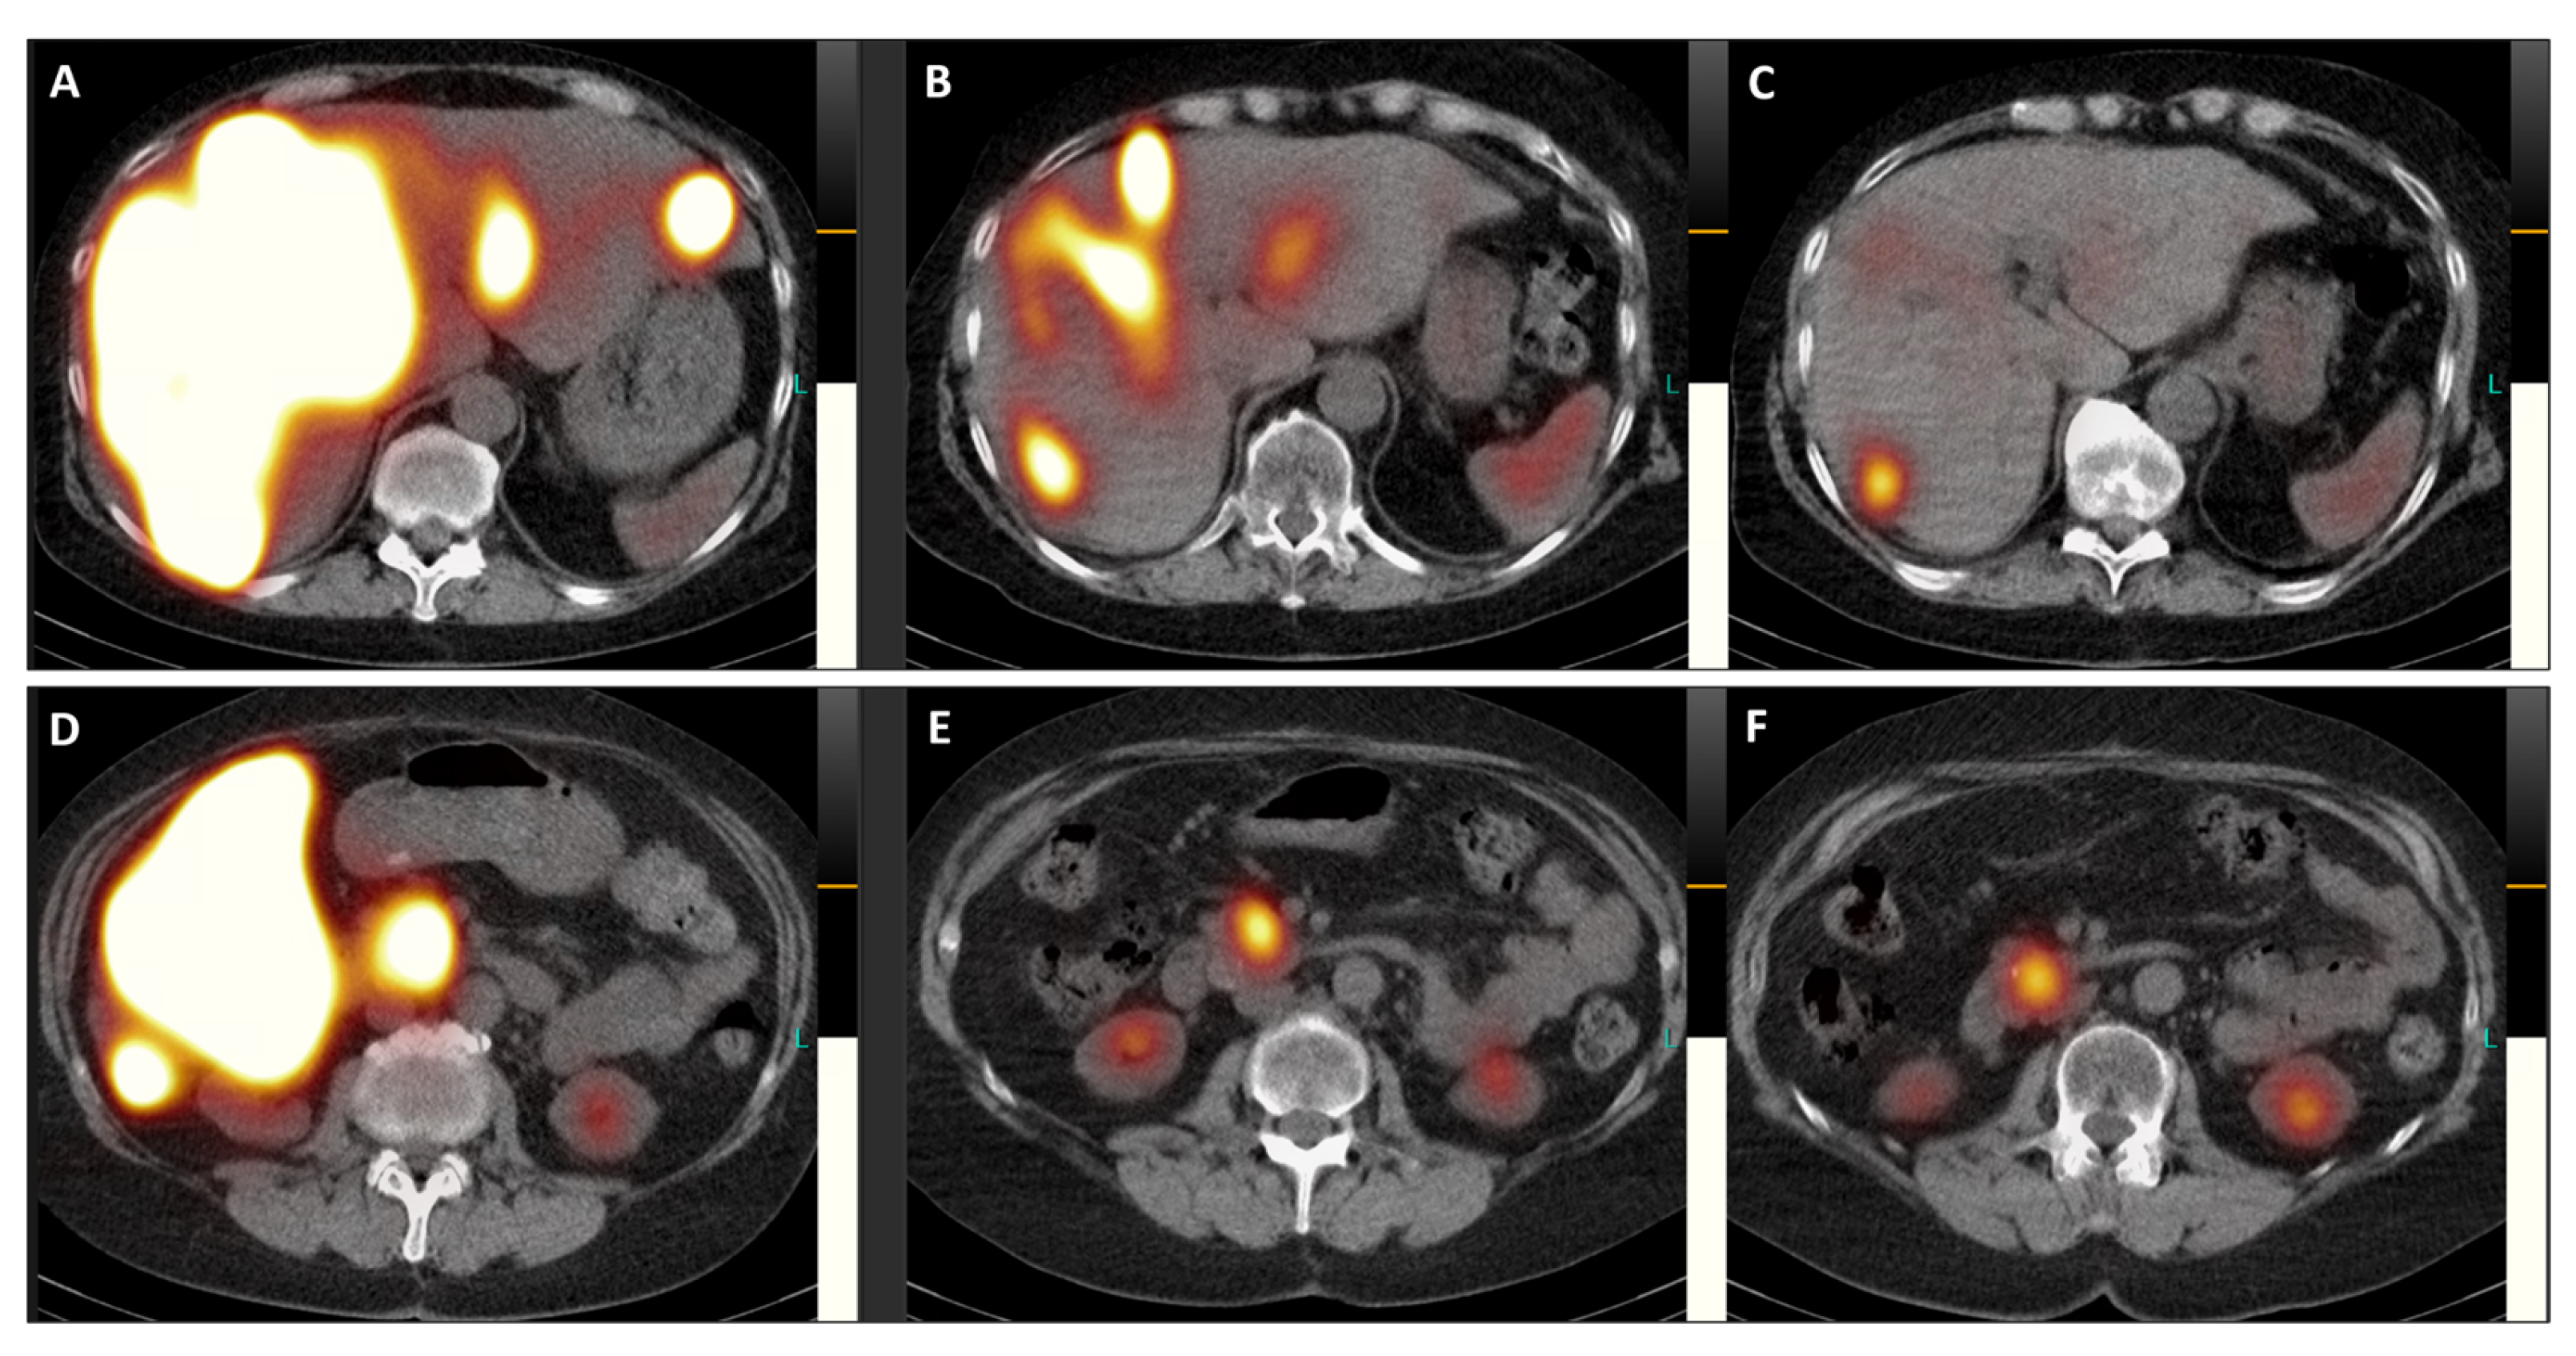

Figure 4. Post-therapeutic coronal SPET/CT scans ((A,D), July 2023; (B,E), September 2023; (C,F), November 2023) illustrate the remarkable improvement in hepatomegaly (with normalization of liver dimensions) and the exceptional reduction in SSTR antagonist uptake in the numerous disseminated metastases across both liver lobes (Figure 4). Additionally, the previously active metastatic lesion in the left transverse process of L5 is no longer visible (AC), and qualitative evaluation indicated a significant decrease in radiotracer uptake in the primary tumor of the pancreatic head (DF). Furthermore, semi-quantitative assessment using mean counts of the primary tumor mass and background (gluteus muscle) revealed a reduction in the tumor-to-background ratio throughout the TANDEM-PRRT courses, from 73.7 in July 2023 to 19.4 in November 2023.

Figure 5. Transversal images of the post-therapeutic SPET/CT scans (Figure 5, (A,D), July 2023; (B,E), September 2023; (C,F), November 2023) provide a detailed view of the remarkable reduction in SSTR antagonist uptake in both liver lobes and the pancreatic head, accompanied by a decrease in the size of the primary tumor (from 41 × 41 mm in July 2023 to 34 × 34 mm in November 2023).